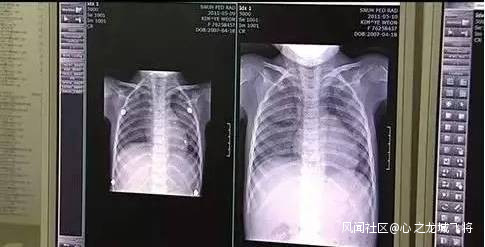

2011年4月,首爾一家醫院接收了17名不明原因的肺炎患者,其中9人接連死亡,多名孕婦出現肺纖維化,韓國民眾一時間陷入流行病恐慌。

之後,韓國疾病管理本部在上述醫院呼吸科、過敏科陸續調查過121名相關症狀住院患者,結果發現,近三四年內,這121名不明原因肺炎患者,每年平均使用加濕器4個月,每次加水時都添加殺菌劑,平均每月使用一瓶殺菌劑。

2011年8月,韓國疾病防控中心確認“兇手”是加濕器殺菌劑。這種含有有毒化學物質的PHMG(聚六亞甲基胍鹽酸鹽)的產品,可導致急性肺部疾病,嚴重可致人死亡。